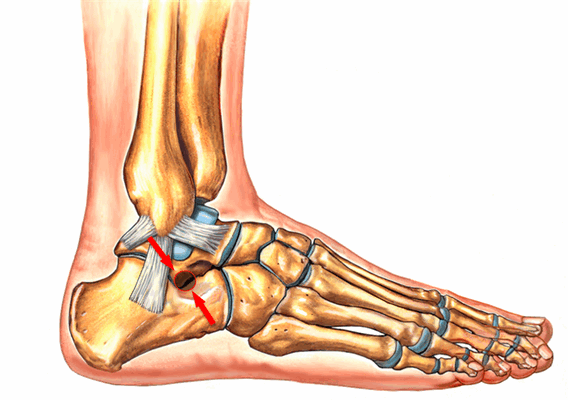

Анатомия повреждения сустава Лисфранка.

Выделяют такие анатомические структуры как связка Лисфранка, сустав Лисфранка и суставной комплекс Лисфранка. Суставной комплекс Лисфранка состоит из предплюсне-плюсневых суставов, межплюсневых суставов, межпредплюсневых суставов.

Наиболее важным моментом в понимании повреждений сустава Лисфранка является осознание критической роли связки Лисфранка в стабилизации не только второго предплюсне-плюсневого сустава но и поддержке всего подошвенного свода. Связка Лисфранка состоит из трёх пучков и связывает медиальную клиновидную кость с основанием второй плюсневой кости. Связка Лисфранка препятствует избыточной пронации и абдукции стопы.

В образовании суставного комплекса Лисфранка также участвуют подошвенные предплюсне-плюсневые связки, тыльные предплюсне-плюсневые связки, межпредплюсневые связки.

За счёт большого количества связок и особенностей строения суставов, суставной комплекс Лисфранка является крайне стабильным с небольшой амплитудой движений.